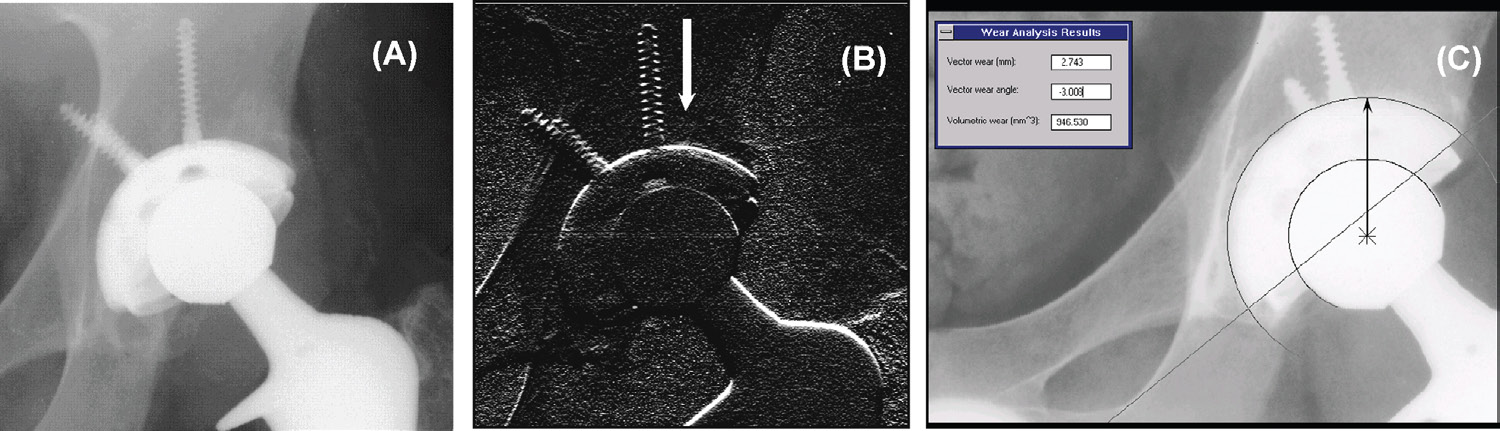

说明了马特尔技术用于计算机辅助测量X光片上的磨损。

采用马特尔和贝尔迪亚方法的计算机辅助放射学磨损测量[32]。(A)磨损分析前的数字放射影像。(B)沿白色箭头方向使用边缘检测器处理数字影像的结果。每个白点代表假体边缘的一个可能位置点。(C)计算机利用上一幅图像生成的边缘点,为髋臼壳和股骨头选择最佳拟合圆。股骨头相对于髋臼中心随时间的位置变化被报告为磨损,并显示在屏幕上。影像由芝加哥大学J. 马丁内尔医生提供,谨此致谢,伊利诺伊州芝加哥市。